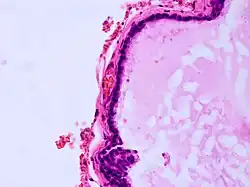

| Histopathology of colloid cyst |

A colloid cyst is a non-malignant tumor in the brain. It consists of a gelatinous material contained within a membrane of epithelial tissue. It is almost always found just posterior to the foramen of Monro in the anterior aspect of the third ventricle, originating from the roof of the ventricle. Because of its location, it can cause obstructive hydrocephalus and increased intracranial pressure. Colloid cysts represent 0.5–1.0% of intracranial tumors.[1]